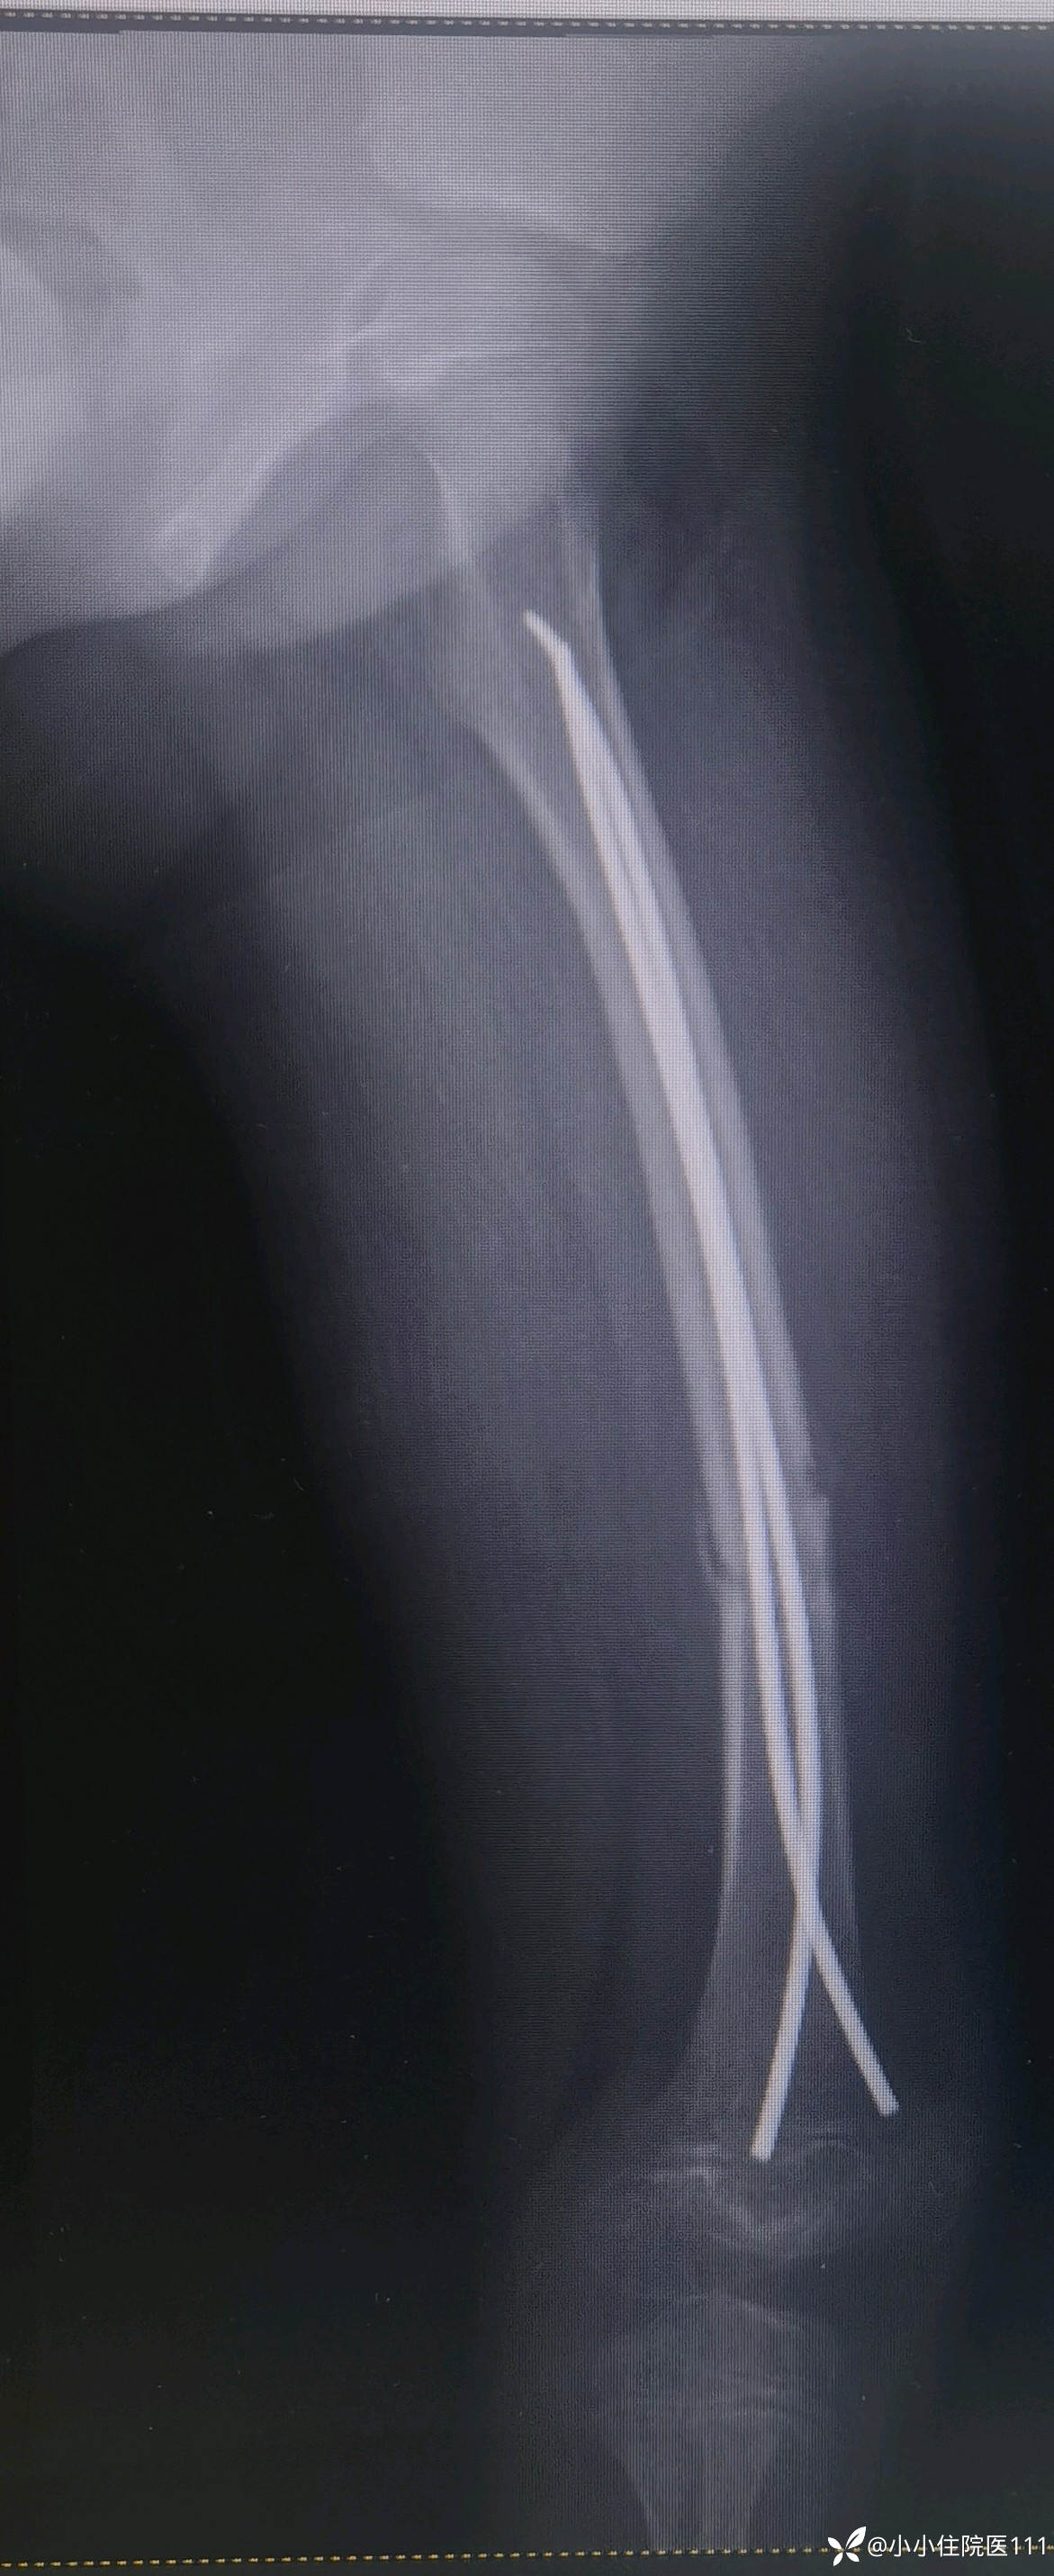

(2023-07-09)复查左股骨正侧位片

(2023-08-28)复查左股骨正侧位片